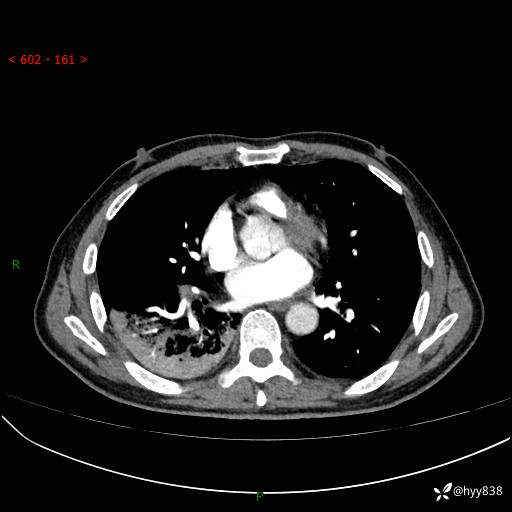

63岁/男,发热5余天。精彩好病例,“大叶性肺炎”,等你来诊---结果公布~

【患者信息】:63岁/男

【主诉】:发热5余天

【现病史及既往史】:患者5余天无明显诱因出现畏寒寒战发热,最高体温39.5℃,发热无明显昼夜规律,伴全身乏力、头晕,无头痛、无咳嗽咳痰、无胸痛咯血、无气短、无腹痛腹泻、无尿频尿急尿痛等不适,于当地市第五人民医院就诊,予以抗感染等治疗(具体不详)后发热无明显好转,1天前查胸部CT提示右下肺感染,为求进一步诊治,门诊以“社区获得性肺炎”收治入院; 起病以来,患者精神、食欲一般,睡眠可,大小便正常,体力体重较前无明显变化。

【检查】:胸部CT增强